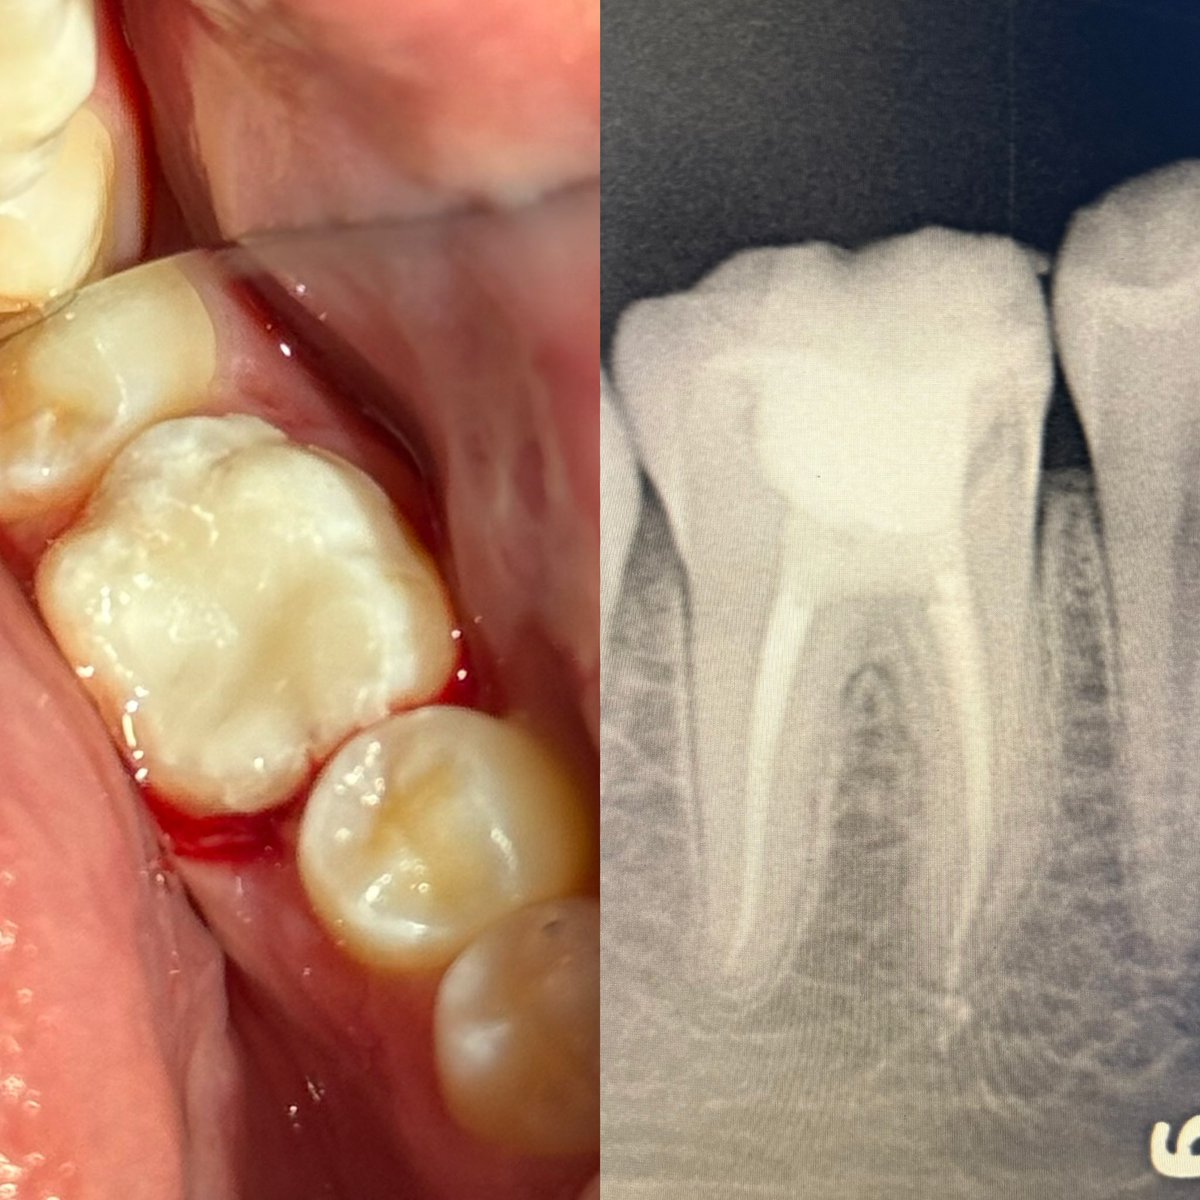

حالة جميلة لصباح اليوم 🙏🏻

Root Canal Treatment #34

Dx:SIP+SAP

Gingival overgrowth and deep caries in the distal wall, Rebuild the distal wall to achieve optimum isolation ✨

Next Step: Crown

#Endodontics